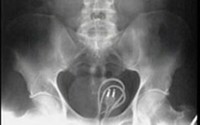

Các bác sĩ khoa ngoại niệu bệnh viện Nhi Đồng 2 TP.HCM vừa nội soi gắp ra một chiếc nhẫn kim loại ở âm đạo của bé gái 7 tuổi. Đó là trường hợp của bé M.N.G.A., nhập viện do viêm âm hộ kéo dài.

Theo lời người nhà, bé tiểu đục và hăm đỏ âm hộ khoảng hơn tháng nay, uống thuốc không giảm. Còn bé A. kể bé bị ngứa cửa mình nên tìm chiếc nhẫn nhét vào cho đỡ ngứa. Qua bệnh sử và thăm khám, các bác sĩ nghi ngờ đây là trường hợp có dị vật sâu bên trong vùng kín của bé nên mới gây viêm nhiễm kéo dài. Hiện bé đã hết tiểu đục và ngứa âm hộ.

ThS.BS Phan Tấn Đức, phẫu thuật viên chính, cho hay các trường hợp dị vật âm đạo khá thường gặp ở bé gái. Nếu không phát hiện sớm, bé sẽ bị viêm nhiễm vùng âm hộ kéo dài, đôi khi tạo các ổ mủ nằm sâu rất khó chữa. Dị vật hoặc do bé té xóc phải hoặc bé tự đưa vào.

Trong trường hợp bé tự đưa vào, có thể do bắt chước người lớn khi thấy nhét thuốc cho em, hoặc có thể là những rối loạn hành vi mắc phải ở trẻ.

Tuy nhiên, một nguyên nhân khác thường gặp và khá phổ biến là bé bị nhiễm giun kim. Giun sẽ từ hậu môn bò sang và chui âm đạo của bé gây ngứa, nên bé sẽ tìm vật gì đó nhét vào để đỡ ngứa. Vì vậy, các bậc cha mẹ nên lưu ý và đưa bé đi khám khi thấy bé tối ngủ không yên hoặc thường hay gãi hoặc sờ mó vùng kín, nhất là bé gái, tránh các trường hợp đáng tiếc xảy ra.